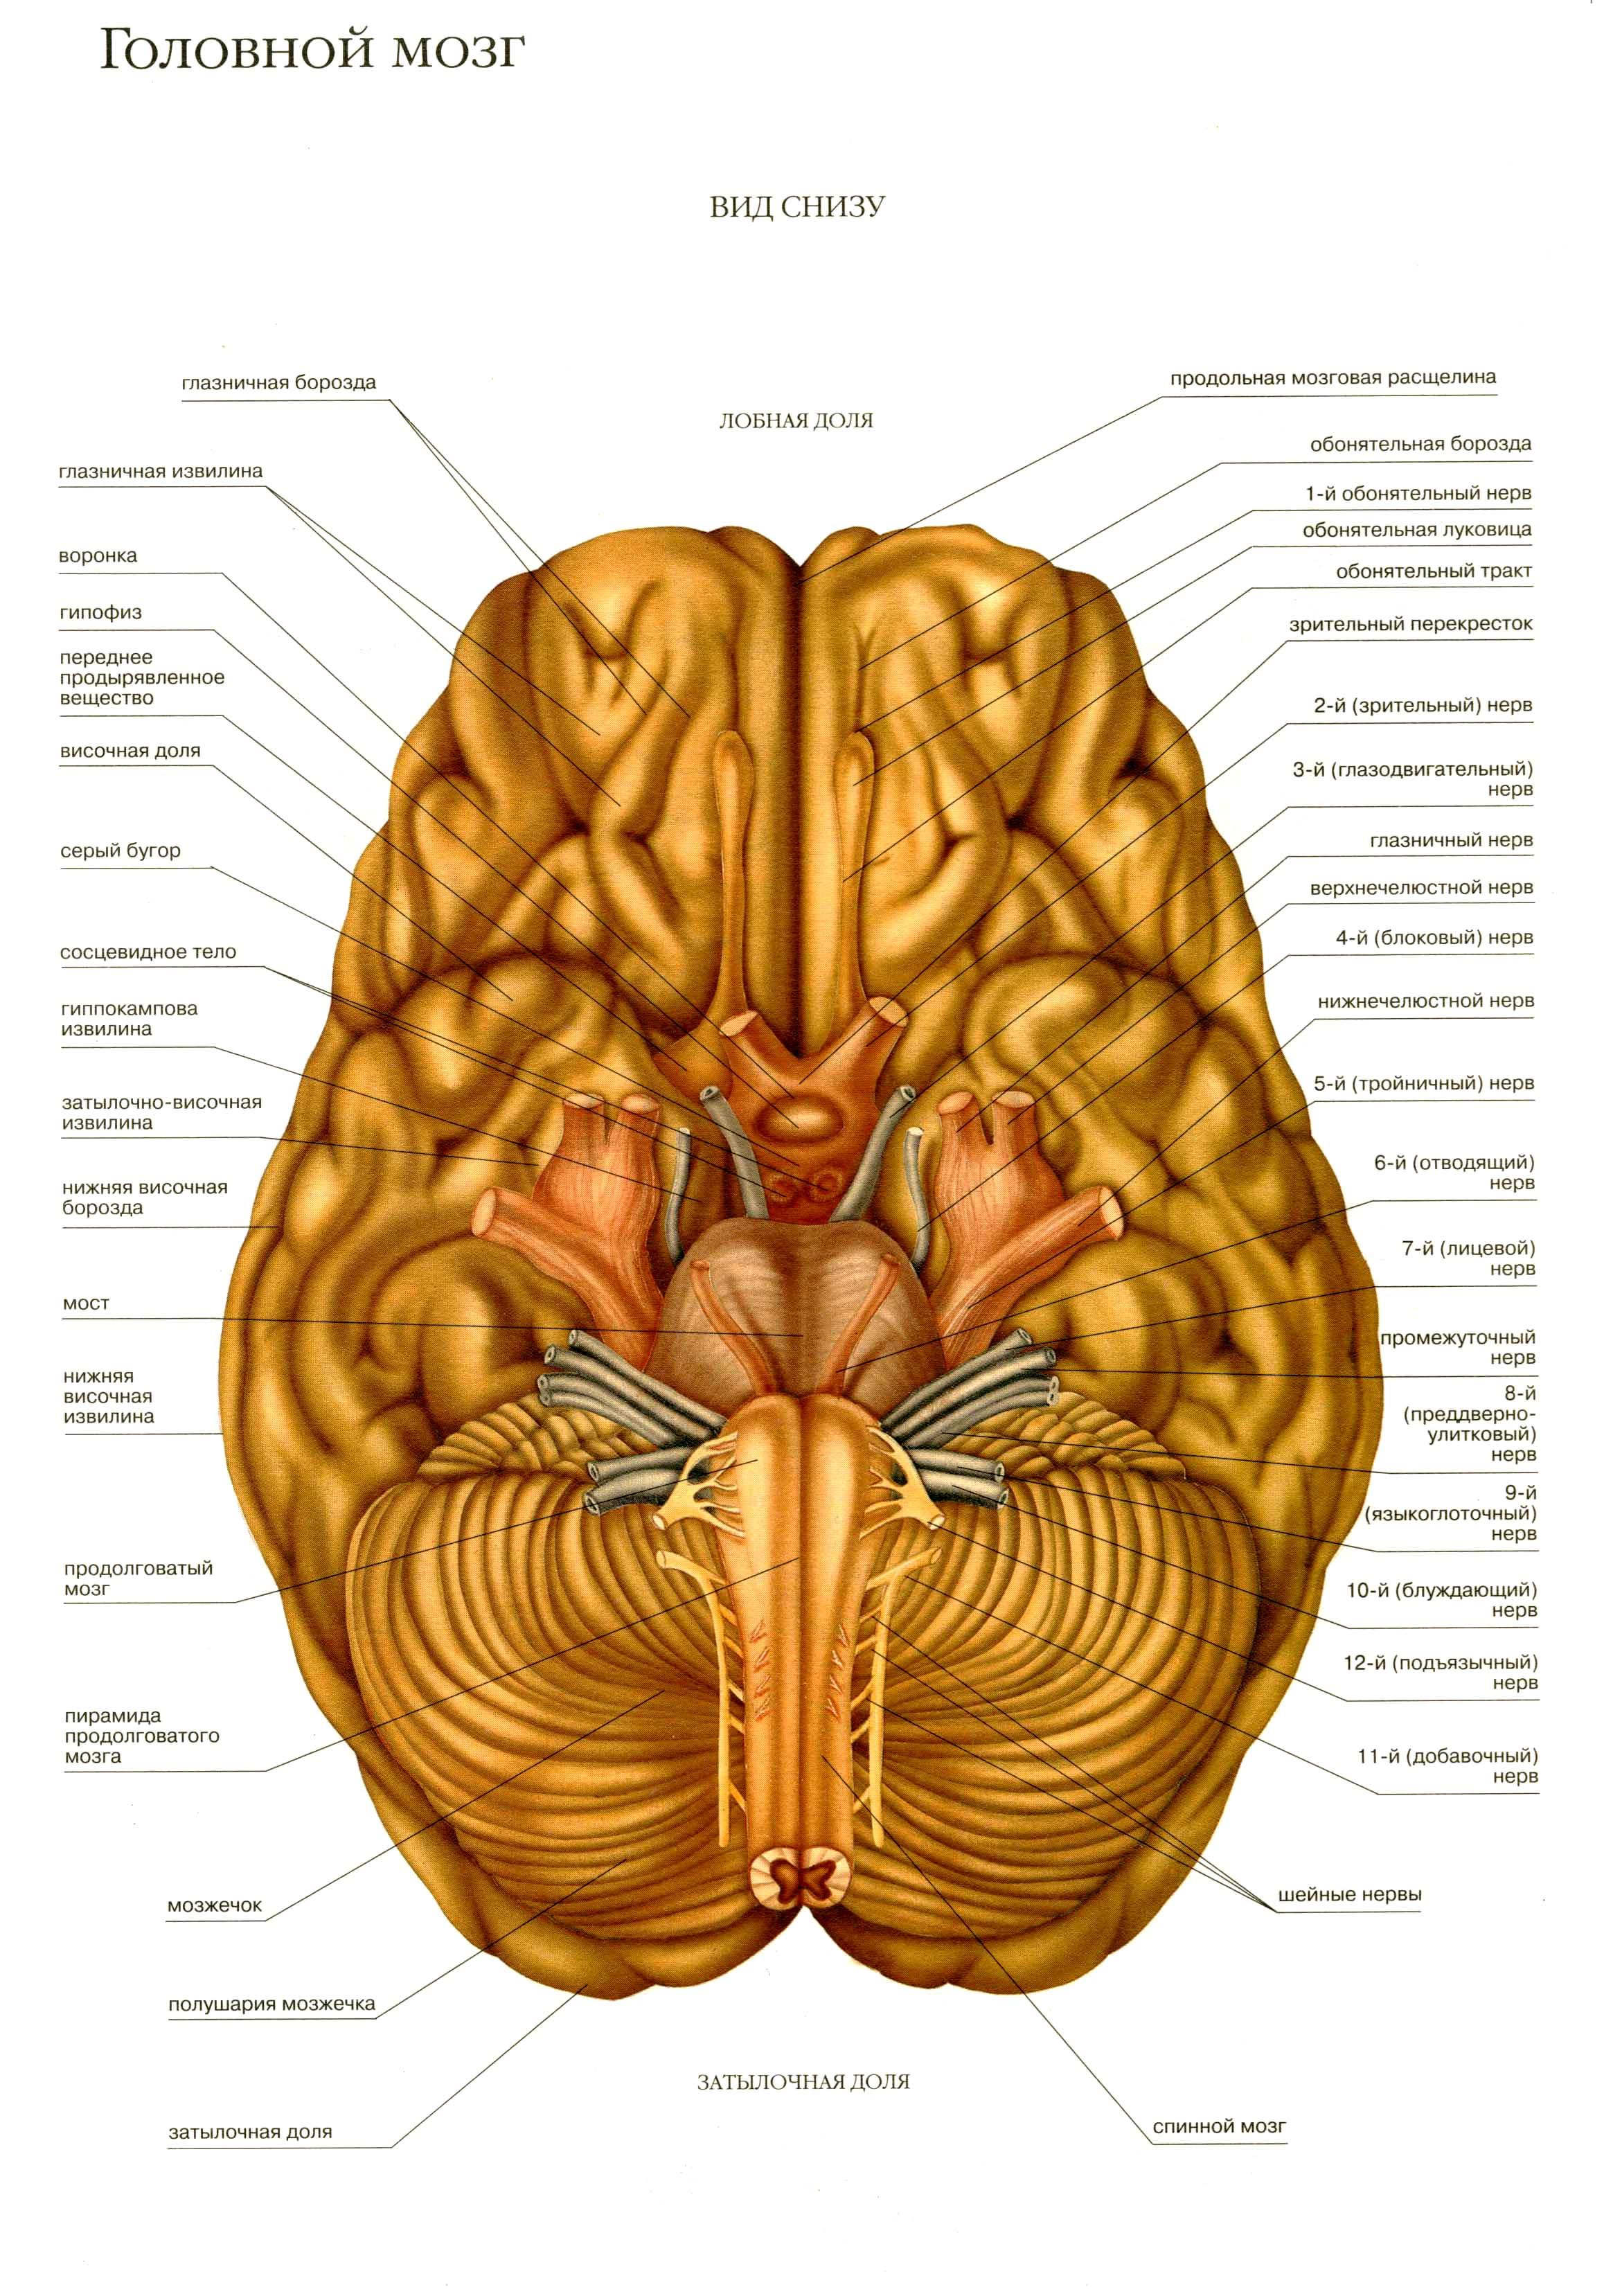

Необычные объекты: Переднее продырявленное вещество